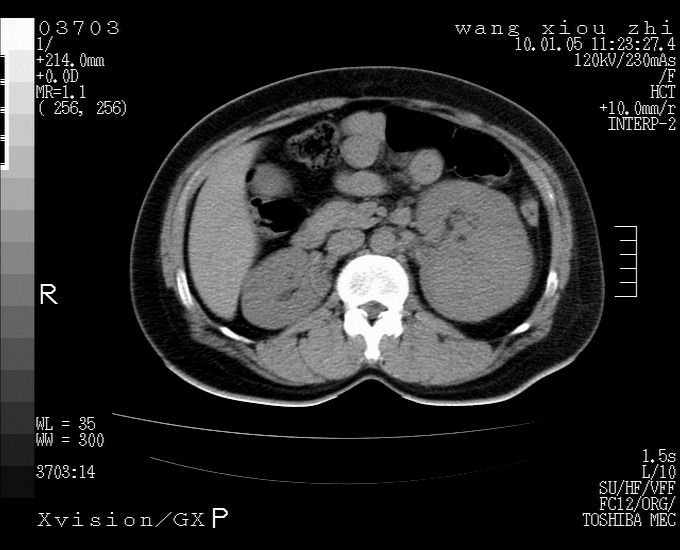

标题: CT23996:f,40.B超提示肿物。 [打印本页]

标题: CT23996:f,40.B超提示肿物。

左肾体积增大!下极见一密度略高团状软组织影!肾周结构组织未见明显异常!考虑左肾占位!建议增强!病史?

左肾占位,肾门及腹膜后淋巴结肿大,考虑透明细胞癌可能性大,建议增强

左肾体积增大,内见肿块影,考虑占位,建议增强。